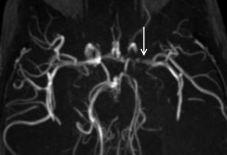

Cerveau

- AVCs ischémiques (200x risque)

- Troubles perfusionnels ++

- Sténoses vasculaires

- Territoires jonctionnels (Carotide++)

- Moya-Moyas